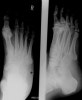

X-ray : Normal calcaneus(Axial view)

X-ray : 종골 골절(Calcaneal fracture)****- Axial view

On the axial view look for fracture lines and breaks in the cortex

Loss of smooth cortical edge (yellow line)